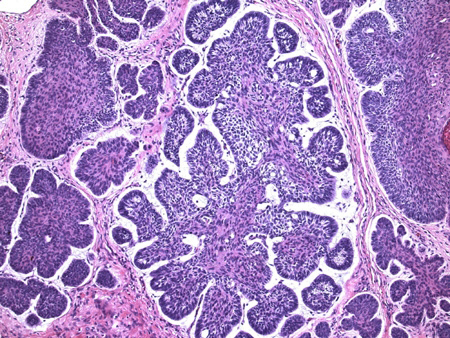

Observam-se aparência histológica do carcinoma basocelular (20x, coloração H-E), divisão estroma-epitélio, distribuição característica dos núcleos em paliçada periférica, além da assim chamada natureza mucinosa do estroma

Do acervo de Drazen M. Jukic, MD, PhD